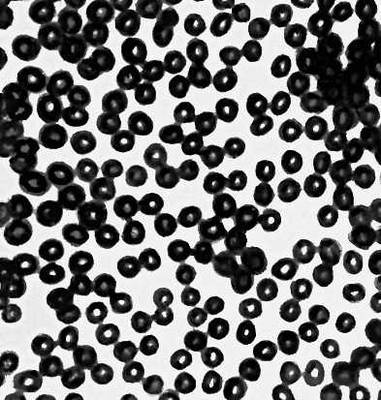

Большая Советская Энциклопедия (УЛ) - i010-001-266604751.jpg

Рис. 5б. Красные кровяные тельца, полученные ультразвуковым микроскопом.